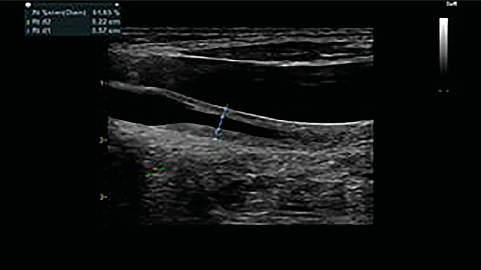

Triplex ultrasound scan of head and neck great vessels: a concentric thickening of the left common carotid artery intima-media, with a hemodynamically significant increase in the blood flow (Fig. 5), stenosis of the distal part of the left subclavian artery, signs of blood flow disturbance the internal jugular vein. CT angiography of the aorta with trunk branches showed similar changes (Fig. 6).

Fig. 5. Concentric thickening of intima-media of left common carotid artery